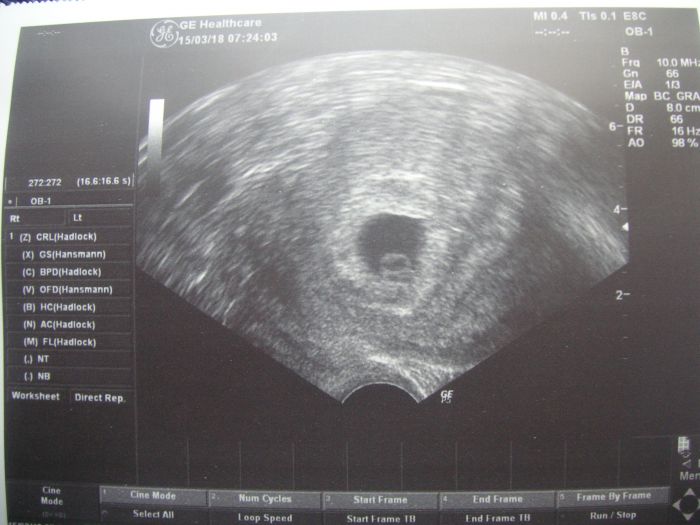

Ahojte, tak sa hlasim prva, som 6+1, vsetko ok, babatko nejakych 5 mm, sediecko bilo. Ja som teda videla len taky pulzujuci fliacik. Dalsia kontrola az o mesiac, ak bude vsetko ok tak knizka. Dufam ze tie co ste boli tiez dnes, ste dopadli podobne dobre :))))

Ahoj holky hlasim kontrola dopadla dobre podle utz jsme 6+5 srdicko bilo a mame 8mm :-) dalsi kontrola 29.3. ale uz u sveho gynekologa,prozatim navsteva v CAR je ukoncena :-)

Ahoj tak kontrola v poradku podle ultz 6+5 srdicko bije..kontrola az za mesic..12.4 jinak ja cekala 2 hodiny v cekarne..je to des u nas